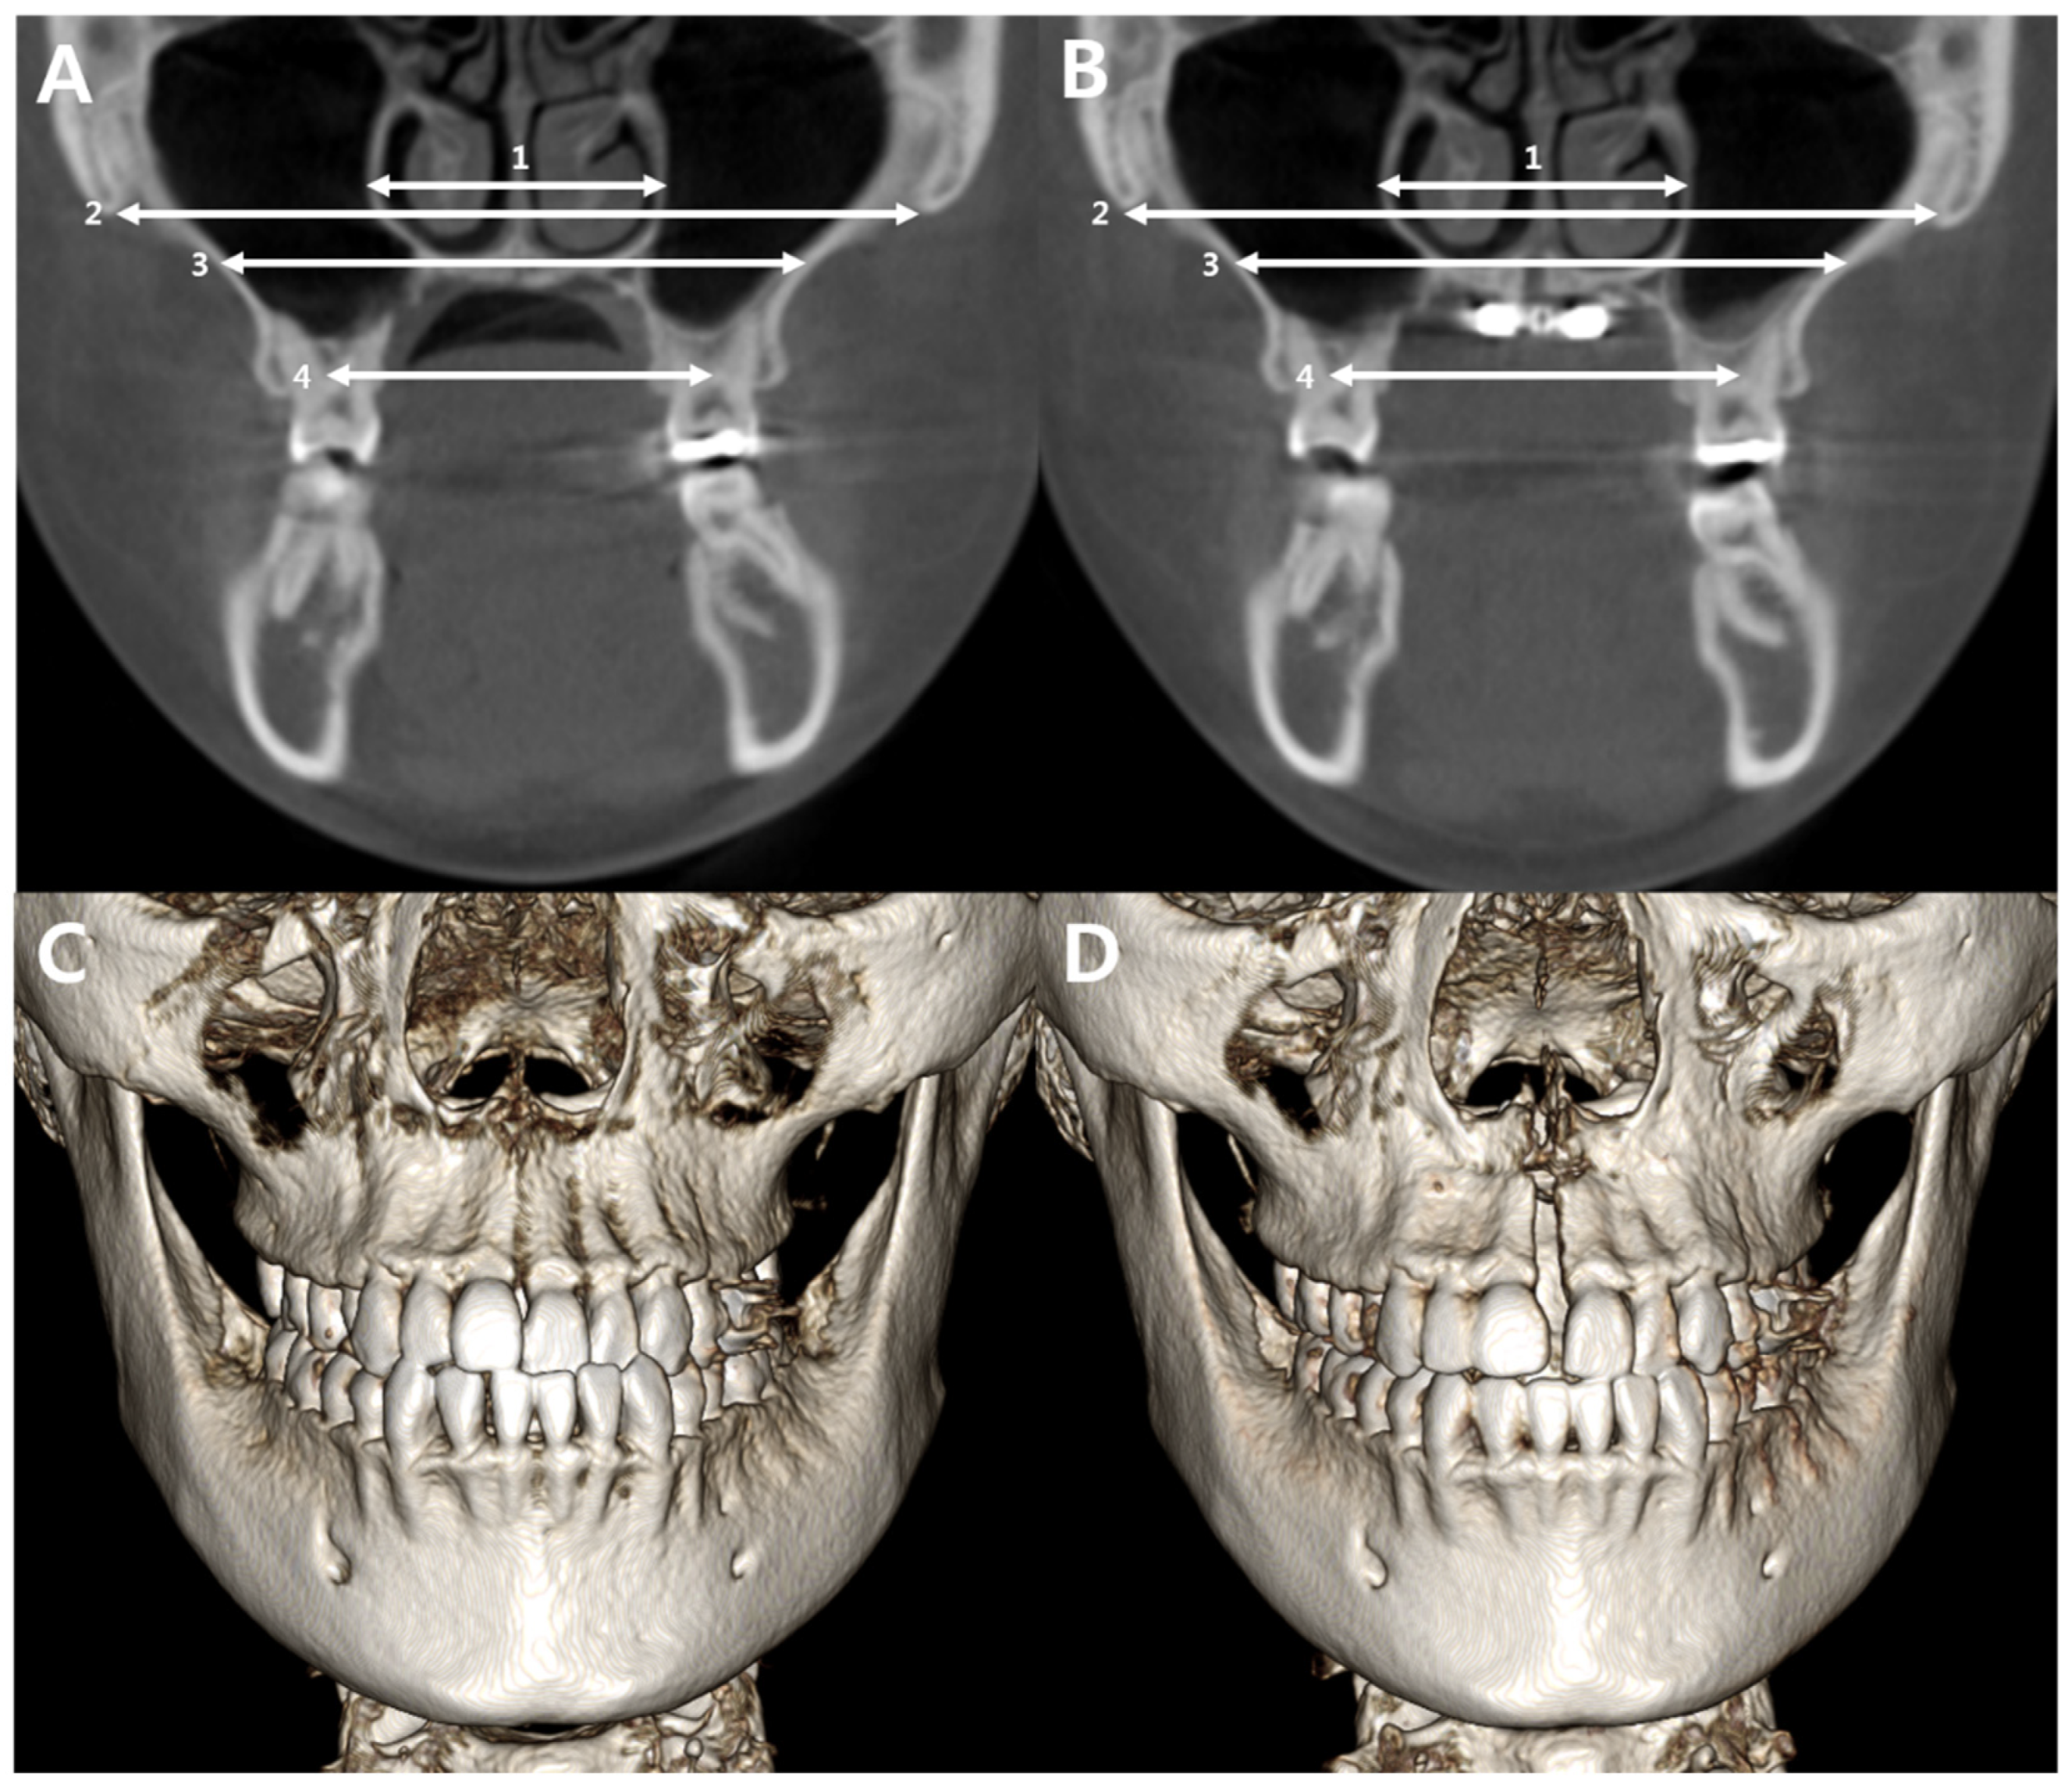

- Cantarella, D.; Dominguez-Mompell, R.; Moschik, C.; Sfogliano, L.; Elkenawy, I.; Pan, H.C.; Mallya, S.M.; Moon, W. Zy-gomaticomaxillary modifications in the horizontal plane induced by micro-implant-supported skeletal expander, analyzed with CBCT images. Prog. Orthod. 2018, 19, 41. [Google Scholar]